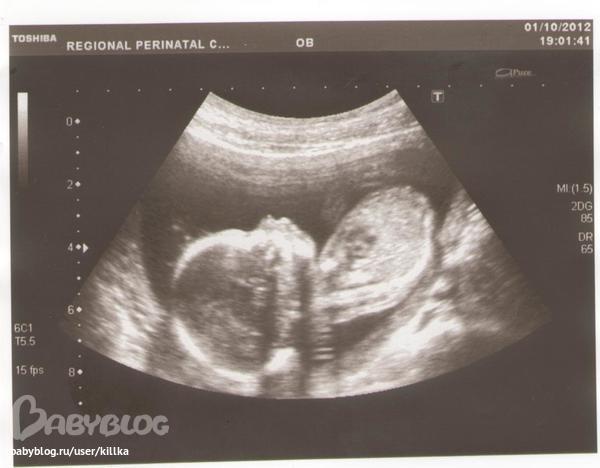

И вот,я уже лежу на кушетке,по животику начинают водить датчиком,врач показывает картинку и говорит: "Ну что,что это такое?",я с такими "пехами" смотрю на экран и говорю-"Не знаю,что это"? (реально не понимаю, так еще и волнуюсь),Ваня смеется,врач тоже)))) И тут я понимаю........у нас будет СЫНИШКА!!!!!!))))))))

Все у нас хорошо (ттт),растем как положено,развиваемся,вертелся и так, и сяк, и что-то жувал, и голову чесал))))Налюбовались нашим солнышком)))))

Мой врач уходит в отпуск,теперь мне на прием в начале ноября, и сразу на 2-ой скрининг,опять встретимся с сыном))))))( как приятно это говорить))))) И наше фото в профиль))))